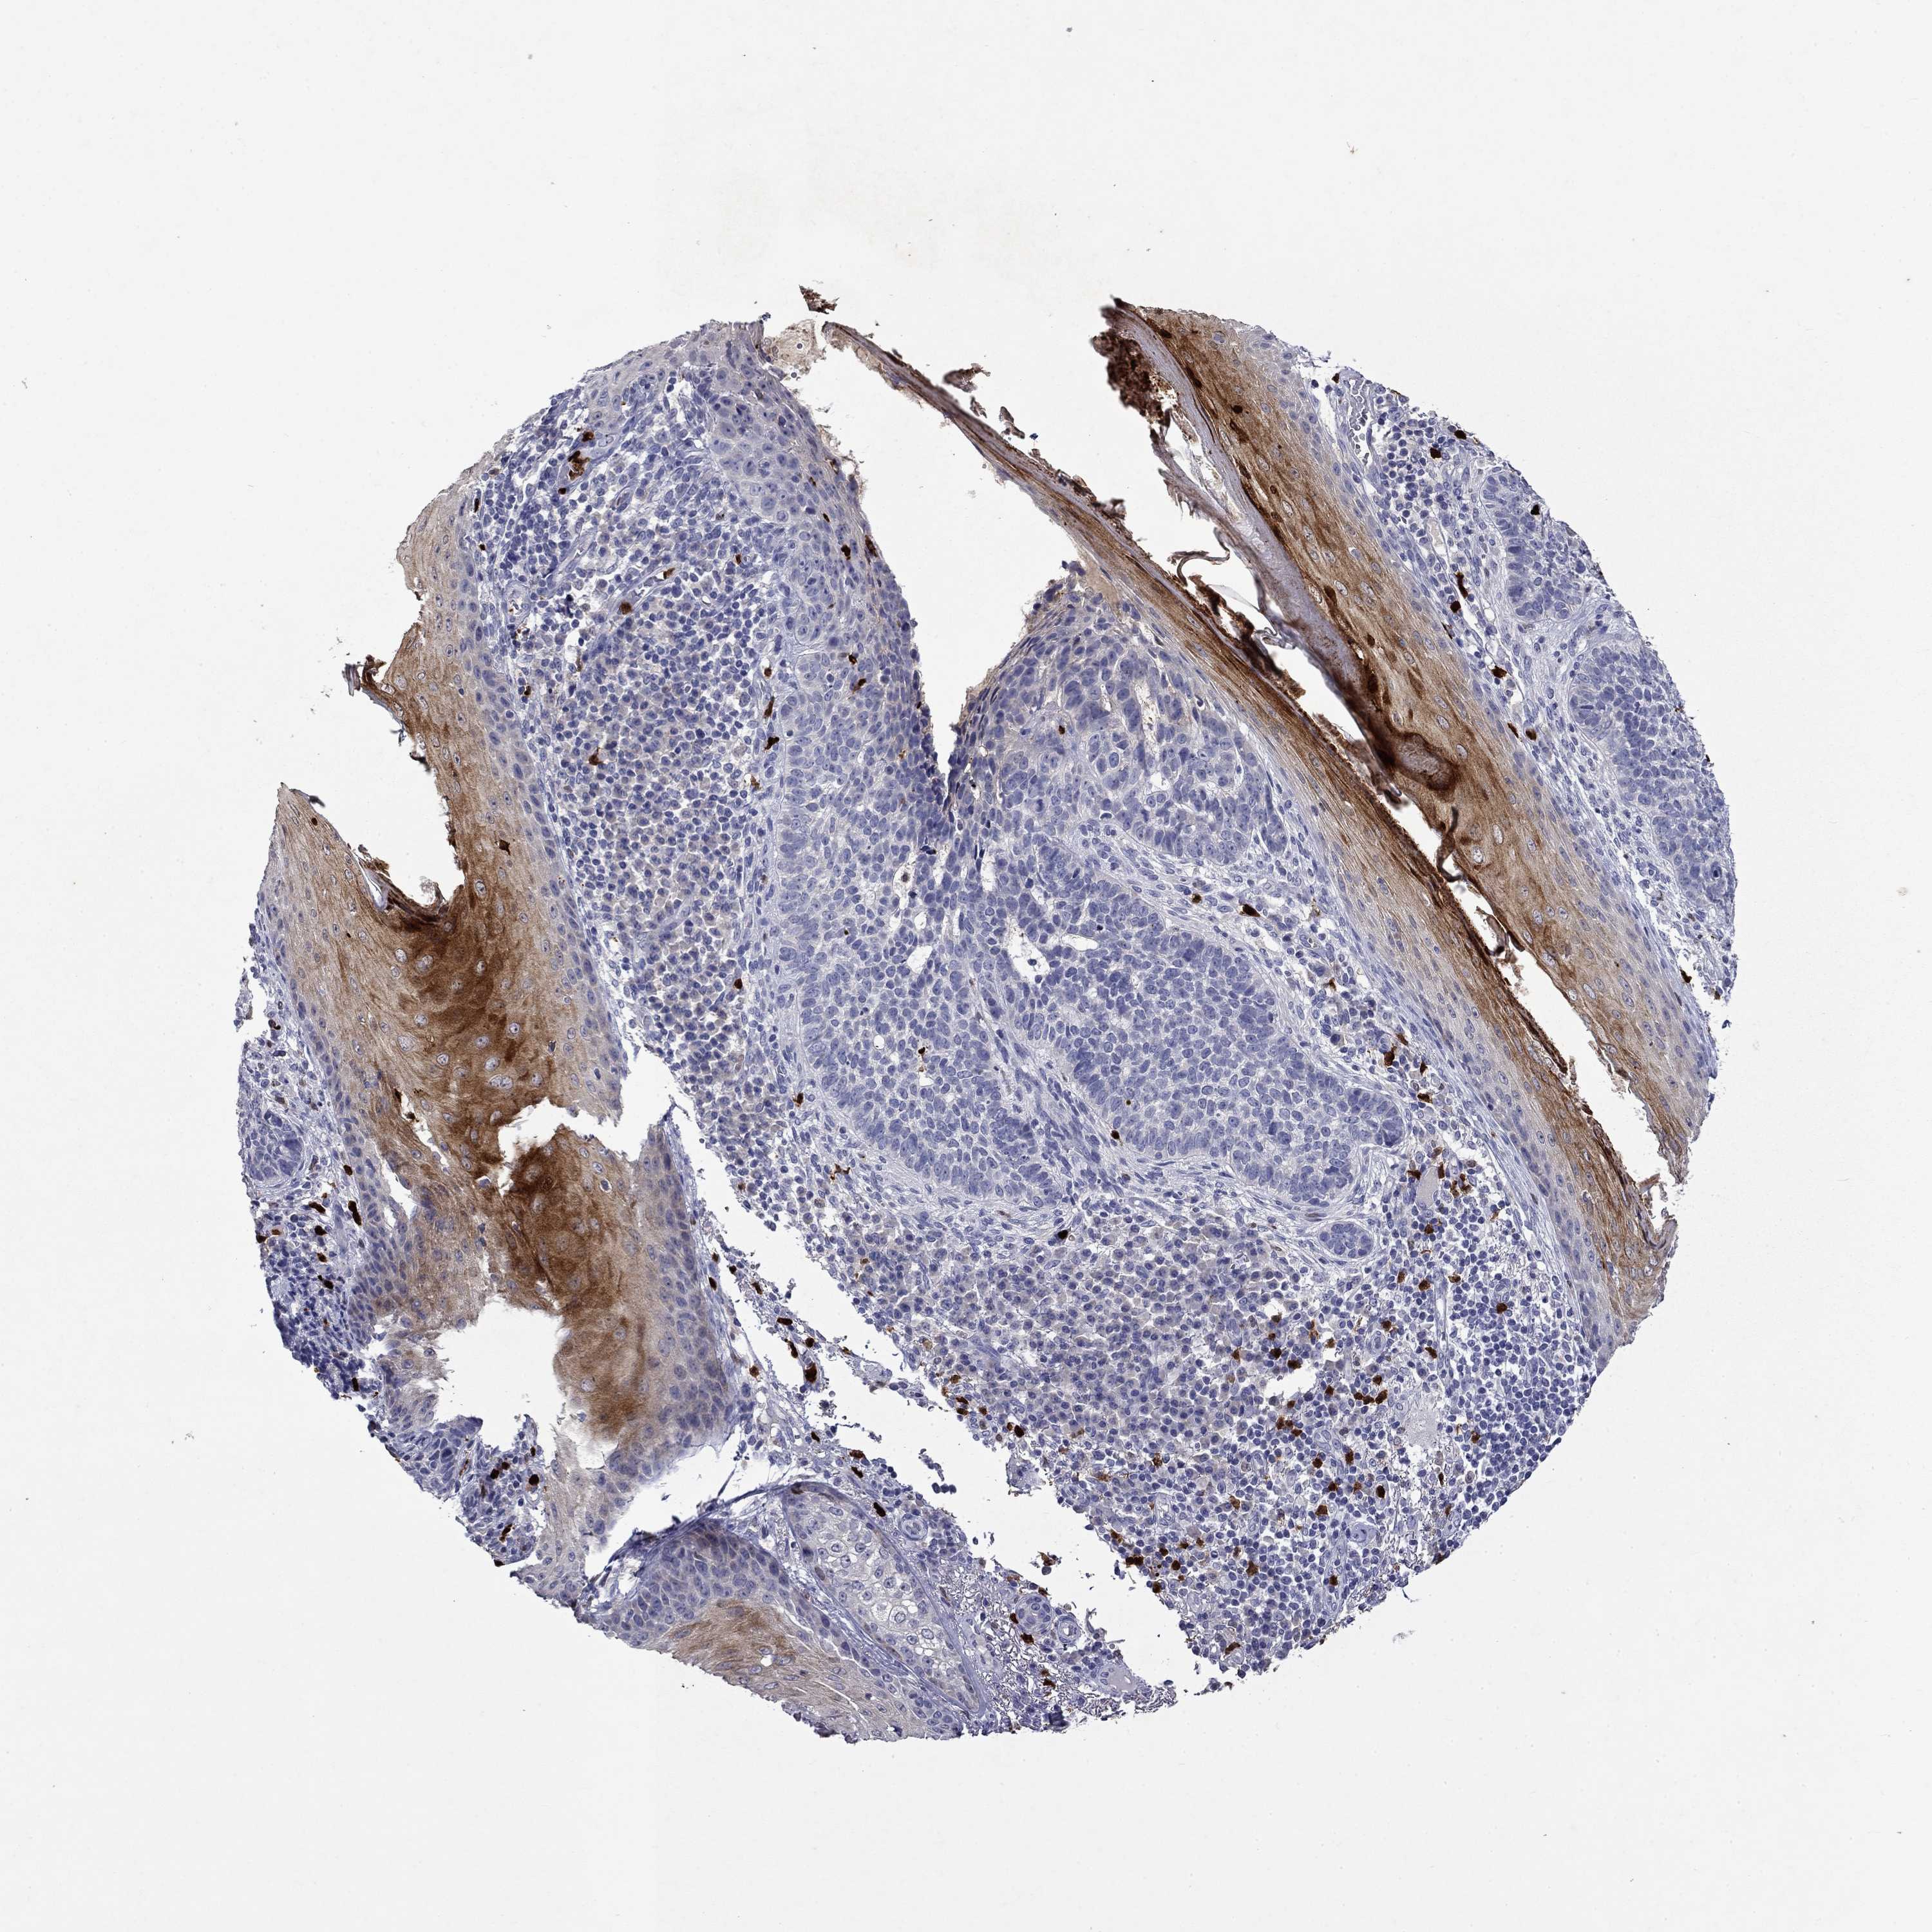

Basal cell and squamous cell cancer

SKIN CANCER - Protein expressioni

A mouse-over function shows sample information and annotation data. Click on an image to view it in a full screen mode. Samples can be filtered based on level of antibody staining by selecting one or several of the following categories: high, medium, low and not detected. The assay and annotation is described here.

Antibody stainingi

Antibody staining in the annotated cell types in the current human tissue is reported as not detected, low, medium, or high, based on conventional immunohistochemistry profiling in selected tissues. This score is based on the combination of the staining intensity and fraction of stained cells.

Each image is clickable and will lead to virtual microscopy that enables deeper exploration of all samples and also displays staining intensity scores, fraction scores and subcellular localization as well as patient and tissue information for each sample.

Antibody HPA046700

Antibody HPA076024

Basal cell carcinoma

Squamous cell carcinoma, NOS

Squamous cell carcinoma, metastatic, NOS